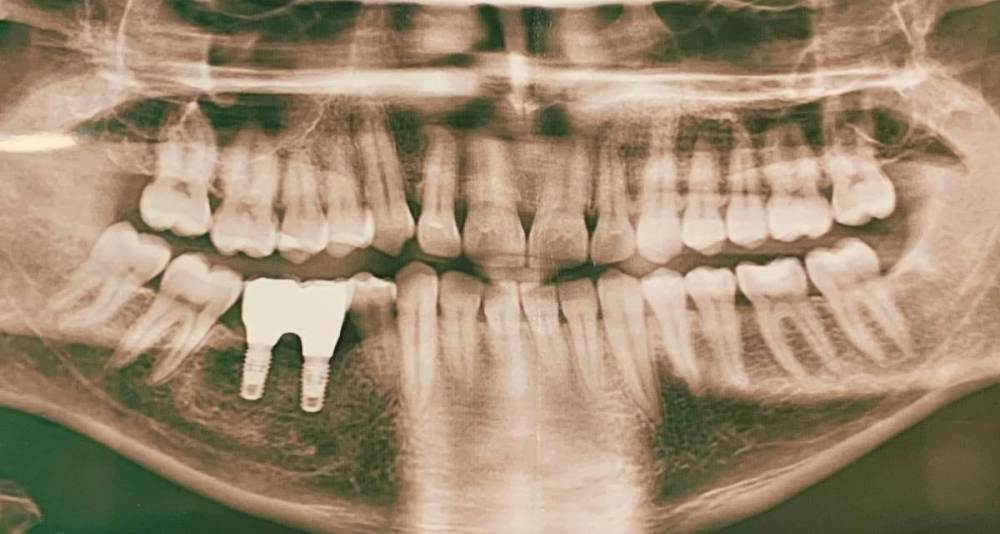

terp3773 Опубликовано 25 июля, 2023 Поделиться Опубликовано 25 июля, 2023 Здравствуйте! Хотелось бы услышать квалифицированное мнение по состоянию зубов. Видно ли критические проблемы на снимке ? Зубы не беспокоят, кроме имплантов. Начало переодически поднывать, но лечащий врач в отпуске.. Хочу услышать Ваши мнения. Благодарю! Ссылка на комментарий

red_butler Опубликовано 26 июля, 2023 Поделиться Опубликовано 26 июля, 2023 20 часов назад, terp3773 сказал: Видно ли критические проблемы на снимке ? нет Ссылка на комментарий